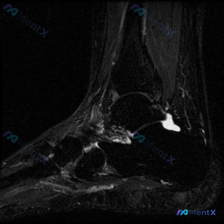

踝关节MRI只看到少量积液?这个病例的鉴别思路其实很容易走偏

今天给大家分享一张踝关节MRI矢状位T2加权影像的读片分析,病例本身并不复杂,但这种仅表现为少量积液的情况,临床其实很容易走偏,整理一下完整的思考过程给大家参考。

这张是踝关节矢状位T2加权MRI,我们先把所有明确的影像信息理清楚:

- 骨骼结构:胫骨远端、距骨、跟骨、舟骨骨皮质完整,没有明显骨折线或骨质破坏;骨髓信号均匀,没有异常的急性骨髓水肿信号

- 关节结构:胫距关节间隙没有明显狭窄,关节面形态尚可,但关节腔内可以看到少量线状高信号,提示存在少量关节积液;跗骨间关节结构没有明显异常

- 肌腱韧带:跟腱、胫骨后肌腱、踇长屈肌腱走行连续,信号均匀,没有撕裂、变性或腱鞘积液的表现;可见的部分韧带结构也没有明确异常

- 软组织:踝关节周围没有广泛软组织水肿,也没有看到异常肿块

核心结论:这张影像唯一的阳性发现就是踝关节腔内少量关节积液,其余结构基本正常,属于表现非常"安静"的影像。